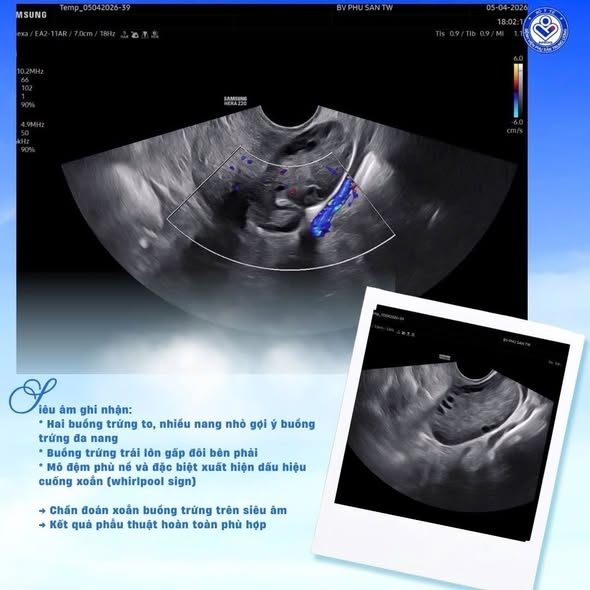

Dù triệu chứng không rầm rộ, nhưng qua thăm khám và siêu âm, các bác sĩ phát hiện hai buồng trứng to, nhiều nang nhỏ gợi ý buồng trứng đa nang, buồng trứng trái lớn hơn rõ rệt, mô đệm phù nề và đặc biệt xuất hiện dấu hiệu cuống xoắn (whirlpool sign).

Mặc dù Doppler vẫn còn tín hiệu mạch – yếu tố dễ gây bỏ sót chẩn đoán, nhưng với kinh nghiệm, sự thận trọng và chuyên môn sâu trong chẩn đoán hình ảnh, các bác sĩ nhận định đây là trường hợp xoắn buồng trứng tái phát và chỉ định phẫu thuật sớm.

Ca bệnh được phát hiện sớm nhờ thăm khám lâm sàng thận trọng kết hợp siêu âm phát hiện dấu hiệu đặc hiệu "whirlpool sign", dù Doppler vẫn còn dòng chảy. Điều này cho thấy không thể loại trừ xoắn buồng trứng chỉ dựa vào Doppler. Sự phối hợp nhanh chóng giữa bác sĩ lâm sàng, chẩn đoán hình ảnh và ê-kíp phẫu thuật đã giúp bệnh nhân được xử trí trong "giờ vàng", tránh biến chứng hoại tử buồng trứng và bảo tồn khả năng sinh sản.